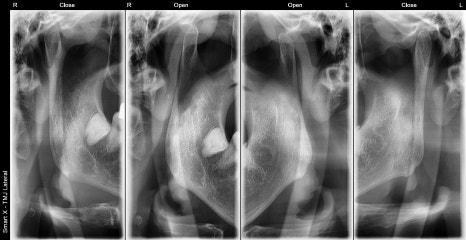

These are the initial X-ray images of a male TMJ patient in his 50s.

Through panoramic and TMJ-specific imaging, abnormal disc positioning (asymmetry) in both TMJs and narrowing of the joint space were confirmed.

The male patient in his 50s visited us with symptoms of “a clicking sound in the jaw and the jaw closing in a zigzag motion every time he chewed.”

At the initial visit,

along with an anatomy-based diagnosis, led to a diagnosis of TMJ disc disorder, and